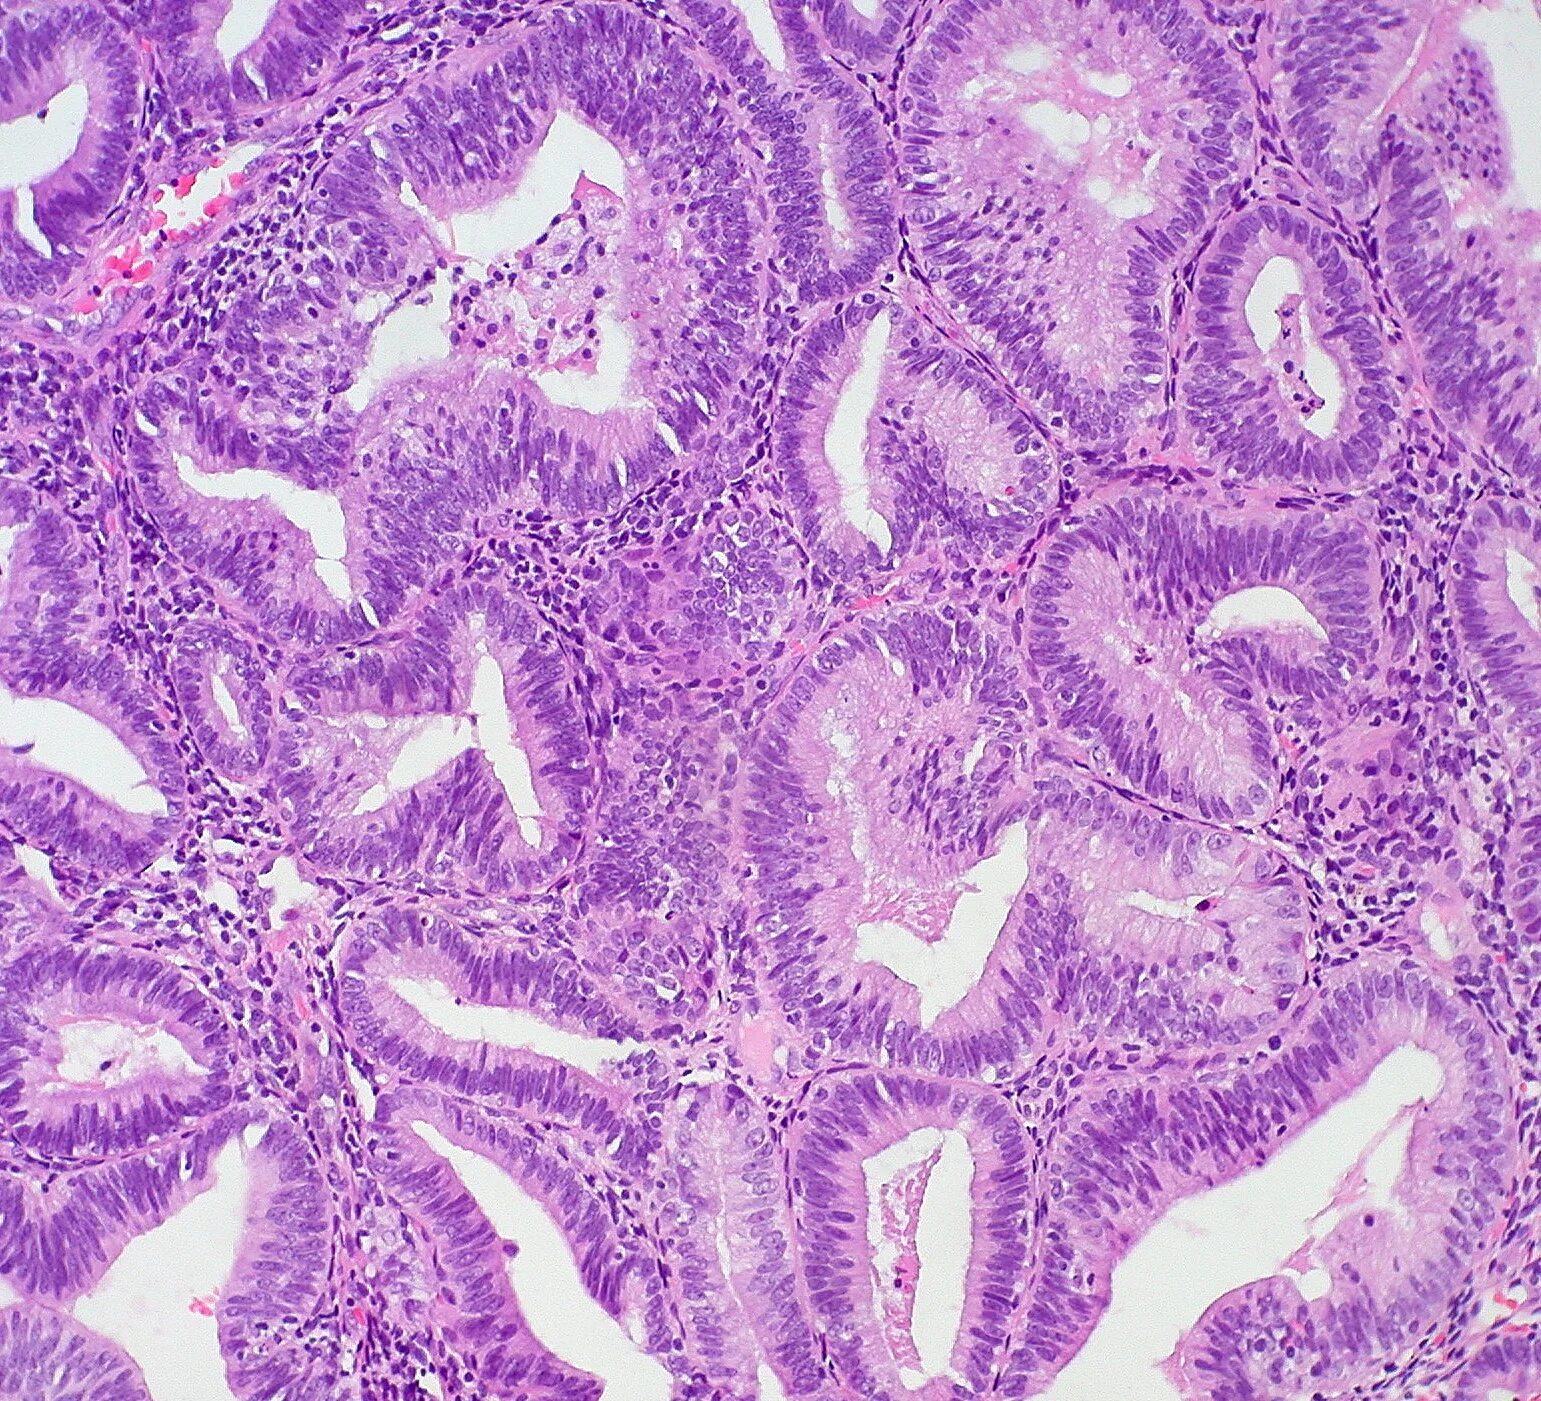

Гистологические варианты